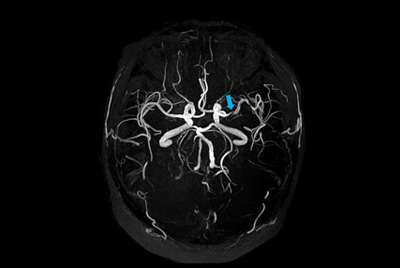

High quality, fast brain aneurysm imaging